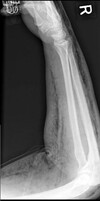

Where does Bronchogenic Carcinoma arise from, and how does it spread?

Arises from mucosa of bronchial tree, metastatic bone spread

What pathology is seen here?

Small Cell Carcinoma -Advanced cases ## Footnote -White large masses; taking up all of the anterior portion of the thorax -Make it harder to breath, move, excsersie

133

Small Cell Carcinoma